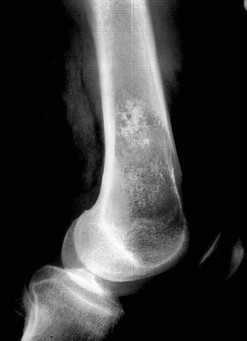

Quel diagnostic pour cette tumeur osseuse?

A

Chondrome de la diaphyse fémorale car matrice cartilagineuse